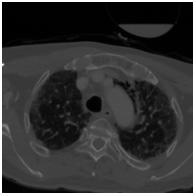

These typical loss functions define the loss of each pixel only on its true and predicted values, but not considering those of other pixels, and aggregate them by weighted averaging or summing without considering the spatial relations between the predictions. Since this type of definition is of local nature, these loss functions may not sufficiently impose a network to learn the shape of an object or the geometry between multiple objects, especially when the amount of training data is small. On the other hand, the ability of the network to learn the shape may be important for better segmenting the objects in medical images since these objects typically have an expected shape or a geometry due to their intrinsic characteristics. One example is the formation of the aortic arch and great vessels in a human body. The aorta and the large arteries and veins (also known as great vessels) are not randomly distributed over the human body. Instead, they are found in a particular geometry due to the human anatomy (Figure 1). Besides, they mostly seem as round objects on a 2D axial image since blood vessels are tubular in 3D. This anatomic information is indeed utilized by human annotators to locate these vessels and delineate their boundaries.

The proposed topology-aware loss function was tested on a dataset that contains CT scans of 24 subjects with prediagnosis of pulmonary embolism. The CT scans were acquired using a 128 slice Philips Ingenuity CT scanner with 1.5 mm slice thickness. A 60 ml of non-ionic contrast material (iohexol; generic name Opaxol) was introduced with a 100 ml saline chaser at 5 ml/s. The data collection was conducted in accordance with the tenets of the Declaration of Helsinki and was approved by Koc University Institutional Review Board (Protocol number: 2022.161.IRB1.064). We randomly split the 24 subjects into the training and test sets. The training set contains 2896 images of 16 subjects; 2234 images of 12 subjects were used to learn the network weights by backpropagation and 662 images of 4 subjects were used as validation images for early stopping. The test set comprises 1431 images of 8 subjects; note that the images of none of these subjects were used neither in the training nor for early stopping.